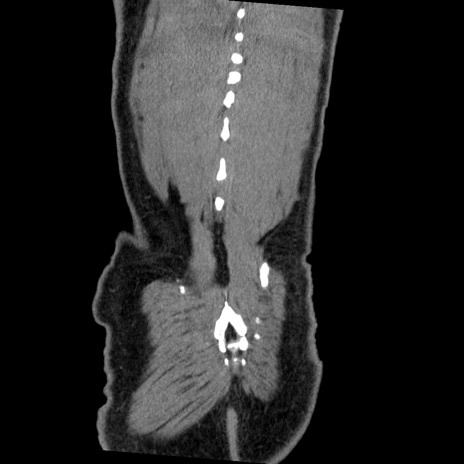

症例22(冠状断像)

【症例】50歳代男性

【主訴】腹痛

【現病歴】AVMからの被殻出血のため回復期リハ病棟入院中。 本日午後3時頃急に下腹部痛が出現した。

【既往歴】AVM、被殻出血、虫垂炎、高血圧

【身体所見】意識晴明、左半身不全麻痺、会話の理解は良好、36.5°C、腹部:膨隆、全体に板状硬、下腹部正中に圧痛点あり、反跳痛-、筋性防御不明、右下腹部にope scar

【データ】WBC 9400、CRP 0.06